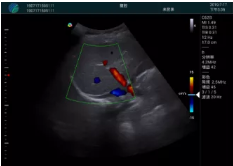

頸動(dòng)脈血流充盈飽滿,無(wú)外溢

肝內(nèi)血管顯示清晰,血流敏感無(wú)外溢